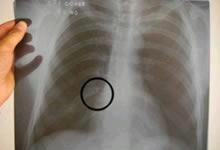

肋骨骨折一般有横型骨折,斜型骨折,螺旋型骨折,三小时后患者呼吸困难,用手捂住骨折处才能敢慢慢呼吸,呼吸有骨擦音,大小便都会疼痛,走路不能直腰,向患侧倾斜身体。